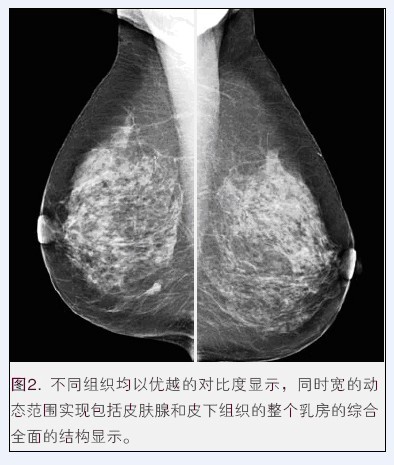

医疗动态